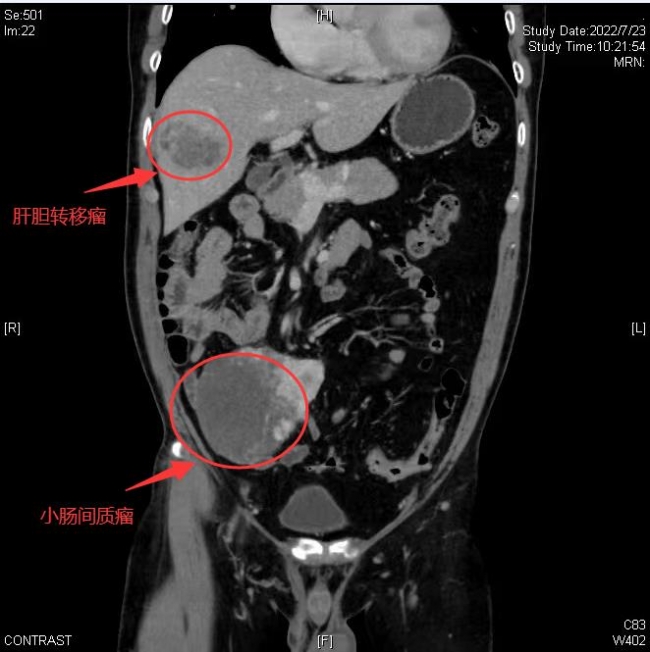

入院后,为明确进一步的诊断,医生详细了解发病经过,为患者完善了更详细的相关检查后,诊断为小肠间质瘤并肝转移,且伴有肝内组织坏死。肝胆外科主任彭钊介绍,“小肠间质瘤分为良性与恶性两种,良性的小肠间质瘤的治疗方案主要以手术治疗为主;而恶性的小肠间质瘤是一种高度的恶性肿瘤,早期易发生转移,当出现肝转移时,病情一般已经处于小肠间质瘤的晚期,大多数患者将失去治疗的机会。而吴大叔的病情虽然已经出现转移,但不是全身广泛性转移,通过手术方式予以治疗,是有机会治愈的。”

为了更好地帮助吴大叔减轻痛苦,彭钊主任团队进行了详细的病例讨论,制定了诊疗方案,同时对吴大叔各项身体健康状态进行了评估。肝脏储备功能实验检查结果显示,吴大叔无肝硬化等基础疾病,身体情况满足肝部分切除条件。经过认真谨慎的联合诊疗讨论,科内专家一致认为吴大叔具有手术指症,肠道、肝脏两处病灶无需进行分期切除,可以实施一次性联合根治手术。

8月2日,肝胆外科团队为吴大叔实施了腹腔镜下右肝前叶肿瘤切除联合小肠巨大间质瘤切除术。术中医务人员密切观测吴大叔生命体征变化,小心翼翼地实施手术,历经4个多小时苦战,终于顺利切除两处病灶,并通过下腹小切口取出标本,手术非常成功!